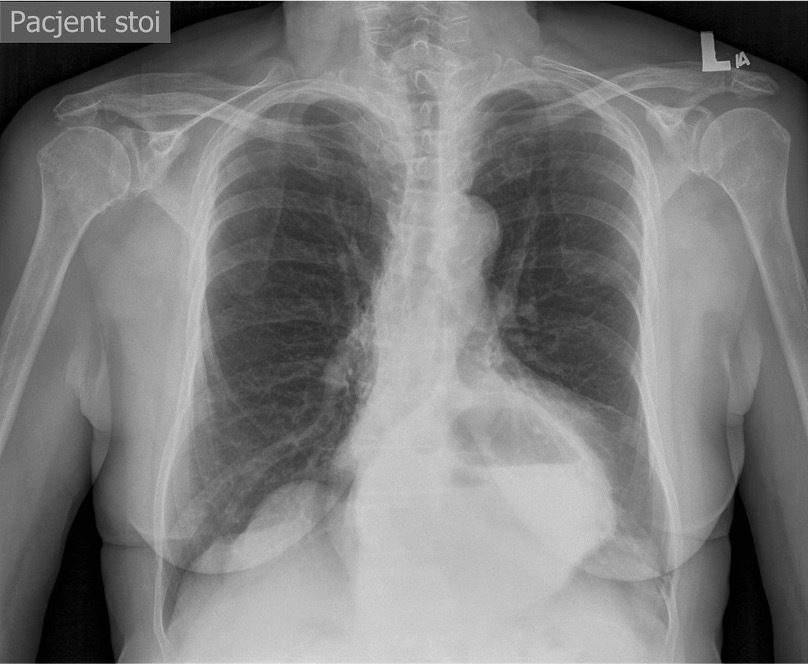

Pneumothorax